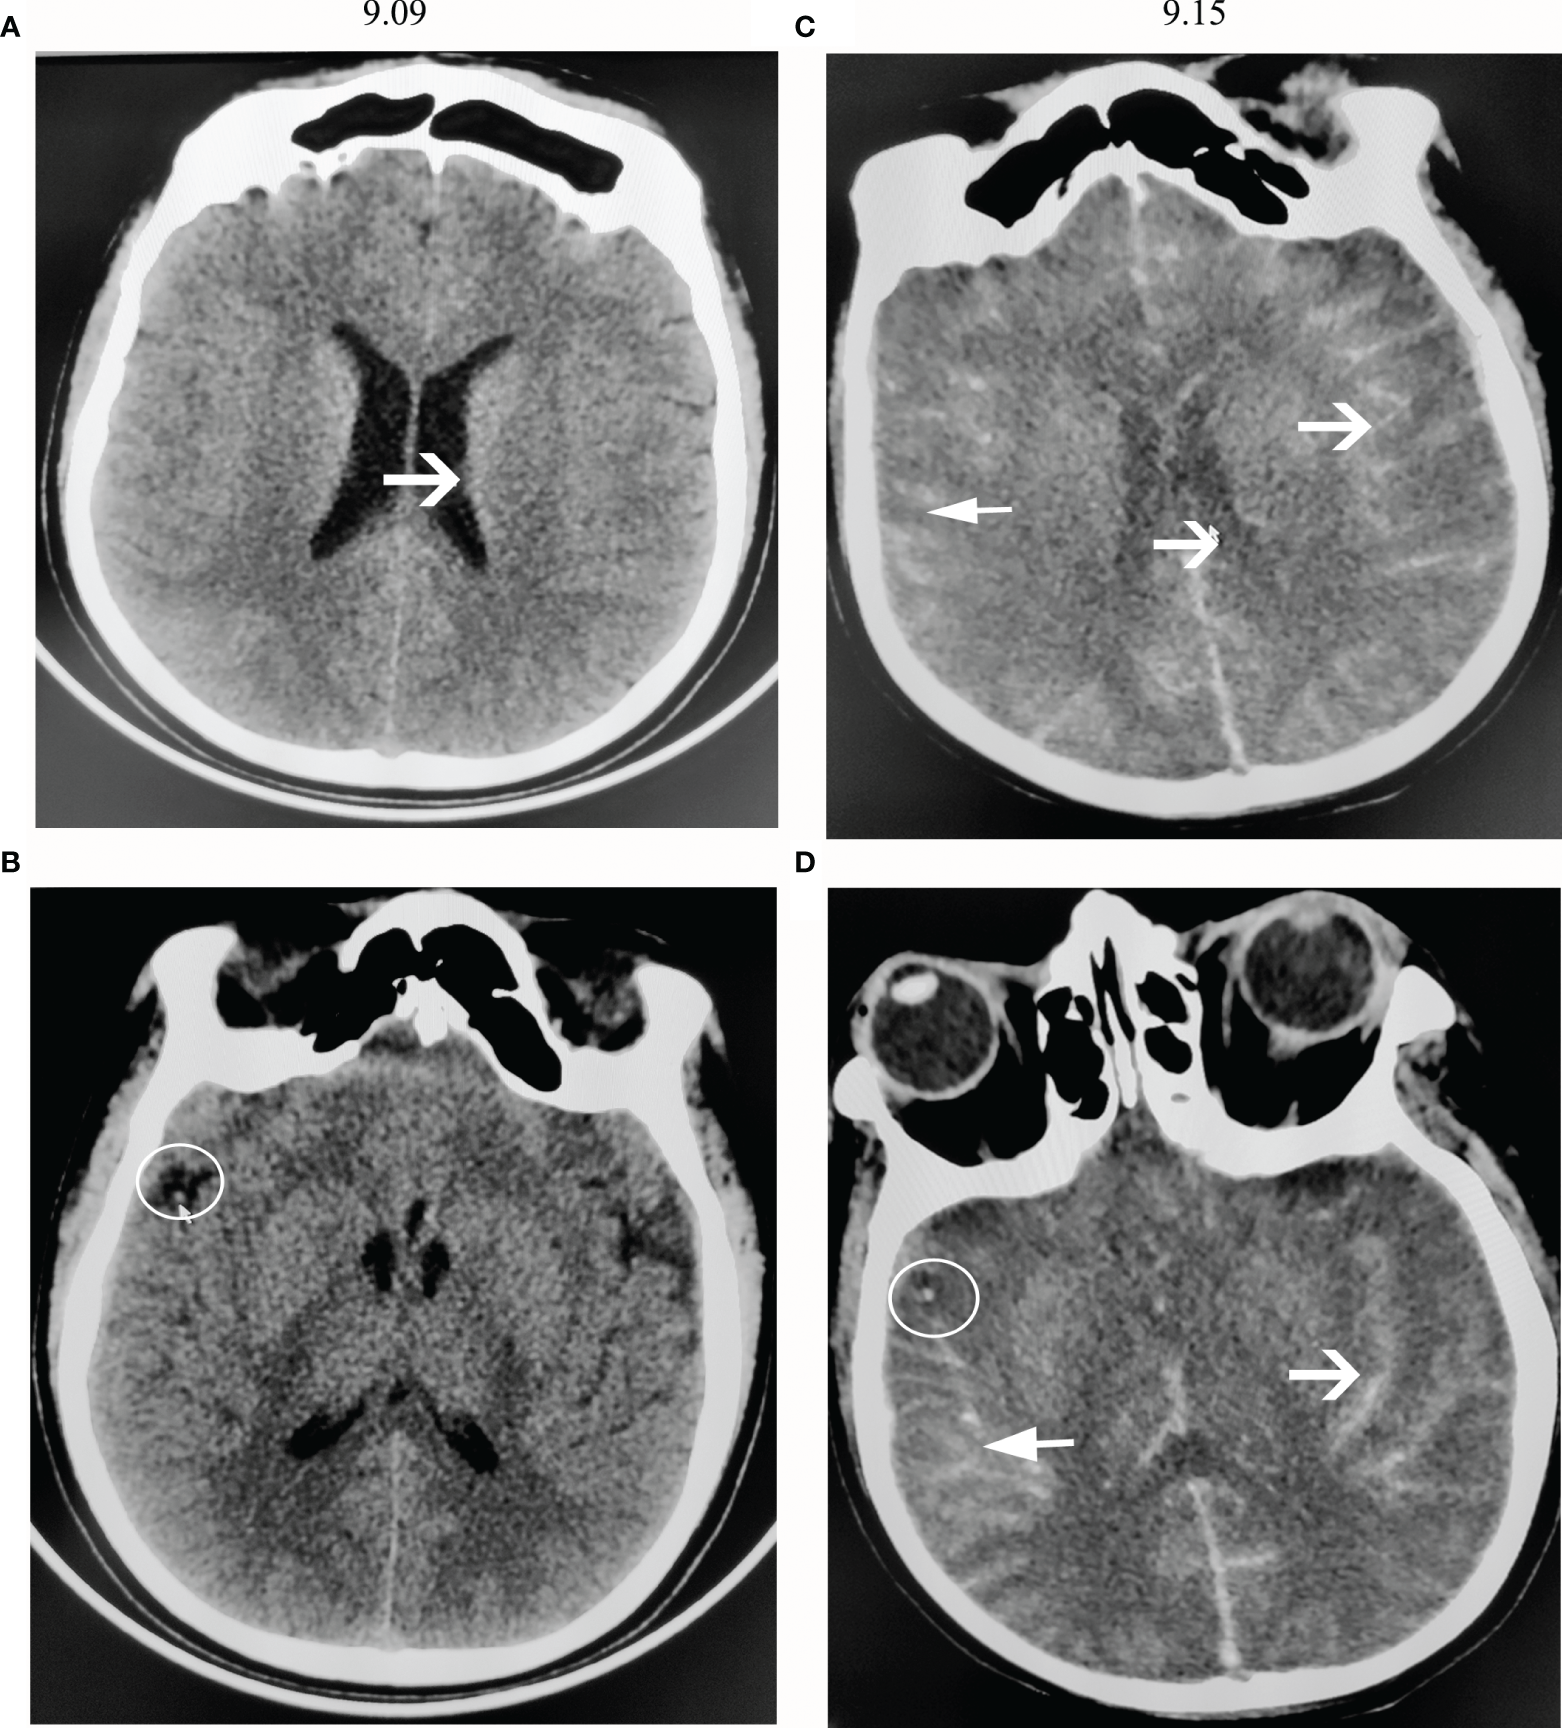

A computed tomography (CT) scan of the brain showed diffuse cerebral edema (Figures 1A, B). The midbrain ventricles had almost disappeared. After 12 h, the man lost consciousness, his right pupil dilated (5 mm), and there was no light reflection. Sixteen hours later, he developed generalized tonic-clonic seizures and experienced dyspnea. He was immediately given endotracheal intubation, requiring ventilator-controlled ventilation. Then, he was admitted to the neurology intensive care unit (NICU).

Figure 1

CT scans of the brain. (A, B) show CT images on the first day of admission (9.09). (C, D) show CT images 6 days after admission (9.15). (A) The brain sulci became obscure, showing diffuse cerebral edema. (B) There was a high-density shadow on the right lateral fissure, as shown by the arrow. (C) The brain sulci showed diffuse subarachnoid hemorrhage, and the lateral ventricles narrowed. (D) A high-density shadow on the right lateral fissure was still present.

When his Na+ concentration returned to normal, somatosensory evoked potential (SSEP) analysis showed that the bilateral N13/P14/N18/N20 disappeared (Figures 2B, C). A computed tomography (CT) scan of the brain showed a diffuse subarachnoid hemorrhage (Figures 1C, D). His clinical features indicated brain death. However, the relatives of the patient did not want to give up, and he was administered amphotericin B liposomes (10 mg-20 mg-40 mg-60 mg/d). During hospitalization, he suffered from severe damage to the liver and kidneys and electrolyte disorders that required CRRT. He died after 3 months. The timeline with relevant data from the episode of care was showed as Figure 4 (supplement).

Our present patient showed generalized brain edema and diffuse subarachnoid hemorrhage on CT scanning. These findings seem to be common. However, due to the rapid progression of PAM and the failure of most patients to undergo MRI, we were looking forward to finding some evidence of early features in CT imaging. Thirty-five cases were identified from PubMed, Web of Science and CNKI that met the criteria. Nineteen of them had detailed clinical data, including CT imaging, as shown in the Table 1-Supplement. The other was our patient. The clinical data and CT features were calculated as shown in Figure 4. The clinical data were as follows: the first symptoms of PAM included headache, fever, and neck stiffness. Sixteen of them experienced headache as their first symptom. All 20 PAM patients suffered from fever. Seventeen of them experienced headache during illness. Additionally, 17 of them had neck stiffness. The CT features were as follows: generalized brain edema or focal edema, hydrocephalus, small or absent ventricle, subarachnoid hemorrhage and erosion of the sphenoid sinus. Most PAM patients suffer from generalized brain edema. Notably, only the patient with focal brain edema survived. Considering the methods of invasion of Naegleria fowleri, the erosion of the sphenoid sinus may theoretically be an early marker of PAM. However, the Neuroimaging staff paid attention to this feature in only one case.

Naegleria fowleri is a ubiquitous, thermophilic, free-living amoeba that is found in many warm freshwater ponds, lakes, streams, and canals. Trophozoites may be inhaled into the nasal cavity, penetrate the nasal mucosa and migrate via the cribriform plate into the central nervous system (CNS) through the olfactory nerves. Then, the mobile trophozoites spread quickly throughout the CNS. Then, this infection causes severe cerebral edema and necrosis and prompts brain herniation. In review articles, all patients who showed generalized brain edema via CT scanning promptly developed brain herniation and died. Our present patient showed the same course. In Chinese cases, only a patient from Hong Kong whose CT scanning showed focal edema (in the right parieto-occipital region) survived (5). Therefore, if the CT images illustrate focal edema, the outcome of PAM may be good. From the reported American cases, the CT or MRI images showed no special features (9). In our review articles, one patient from India showed erosion of the sphenoid sinus (11). The staff in the other cases ignored this feature. Considering the unique invasive route of the organisms causing PAM, whether the sphenoid sinus was destroyed should be noted. Second, most PAM patients showed diffuse subarachnoid hemorrhage. The CSF cytological tests showed dramatically increased numbers of white blood cells with many red blood cells. In our present patient, the CSF sample showed many red blood cells, and CT scanning showed high-density puncta in the right lateral fissure on the day of admission. Then, 5 days after admission, the patient showed diffuse subarachnoid hemorrhage, and the CSF showed many red blood cells around the trophozoites. The above data illustrated that if the CSF sample showed changes similar to those of a bacterial infection and there was subarachnoid hemorrhage at the same time, PAM should be considered.